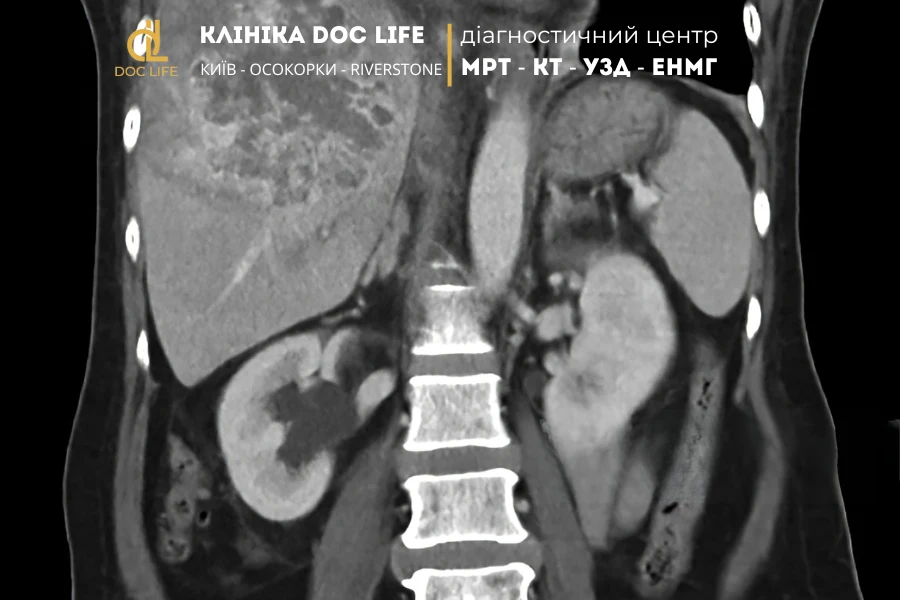

Метастазы в печени

На МРТ с контрастом видны как множественные округлые очаги с контрастным ободком по периферии и гипоинтенсивным центром (зона некроза). Это наиболее частый тип поражений печени при онкологических заболеваниях других органов.

МРТ печени с контрастом позволяет выявить широкий спектр патологий — от опасных форм рака до доброкачественных образований, не представляющих угрозы жизни.

По характеру накопления контраста врач определяет природу опухоли, стадию заболевания и выбирает оптимальную тактику лечения без необходимости в биопсии.

Медицинский центр Doc Life проводит МРТ в Киеве на современном томографе Siemens Sempra 1.5T.

Для диагностики метастазов и опухолей печени используются два вида контрастных препаратов немецкого производства — Гадовист и Примовист, которые обеспечивают максимальную точность визуализации и безопасность пациента.